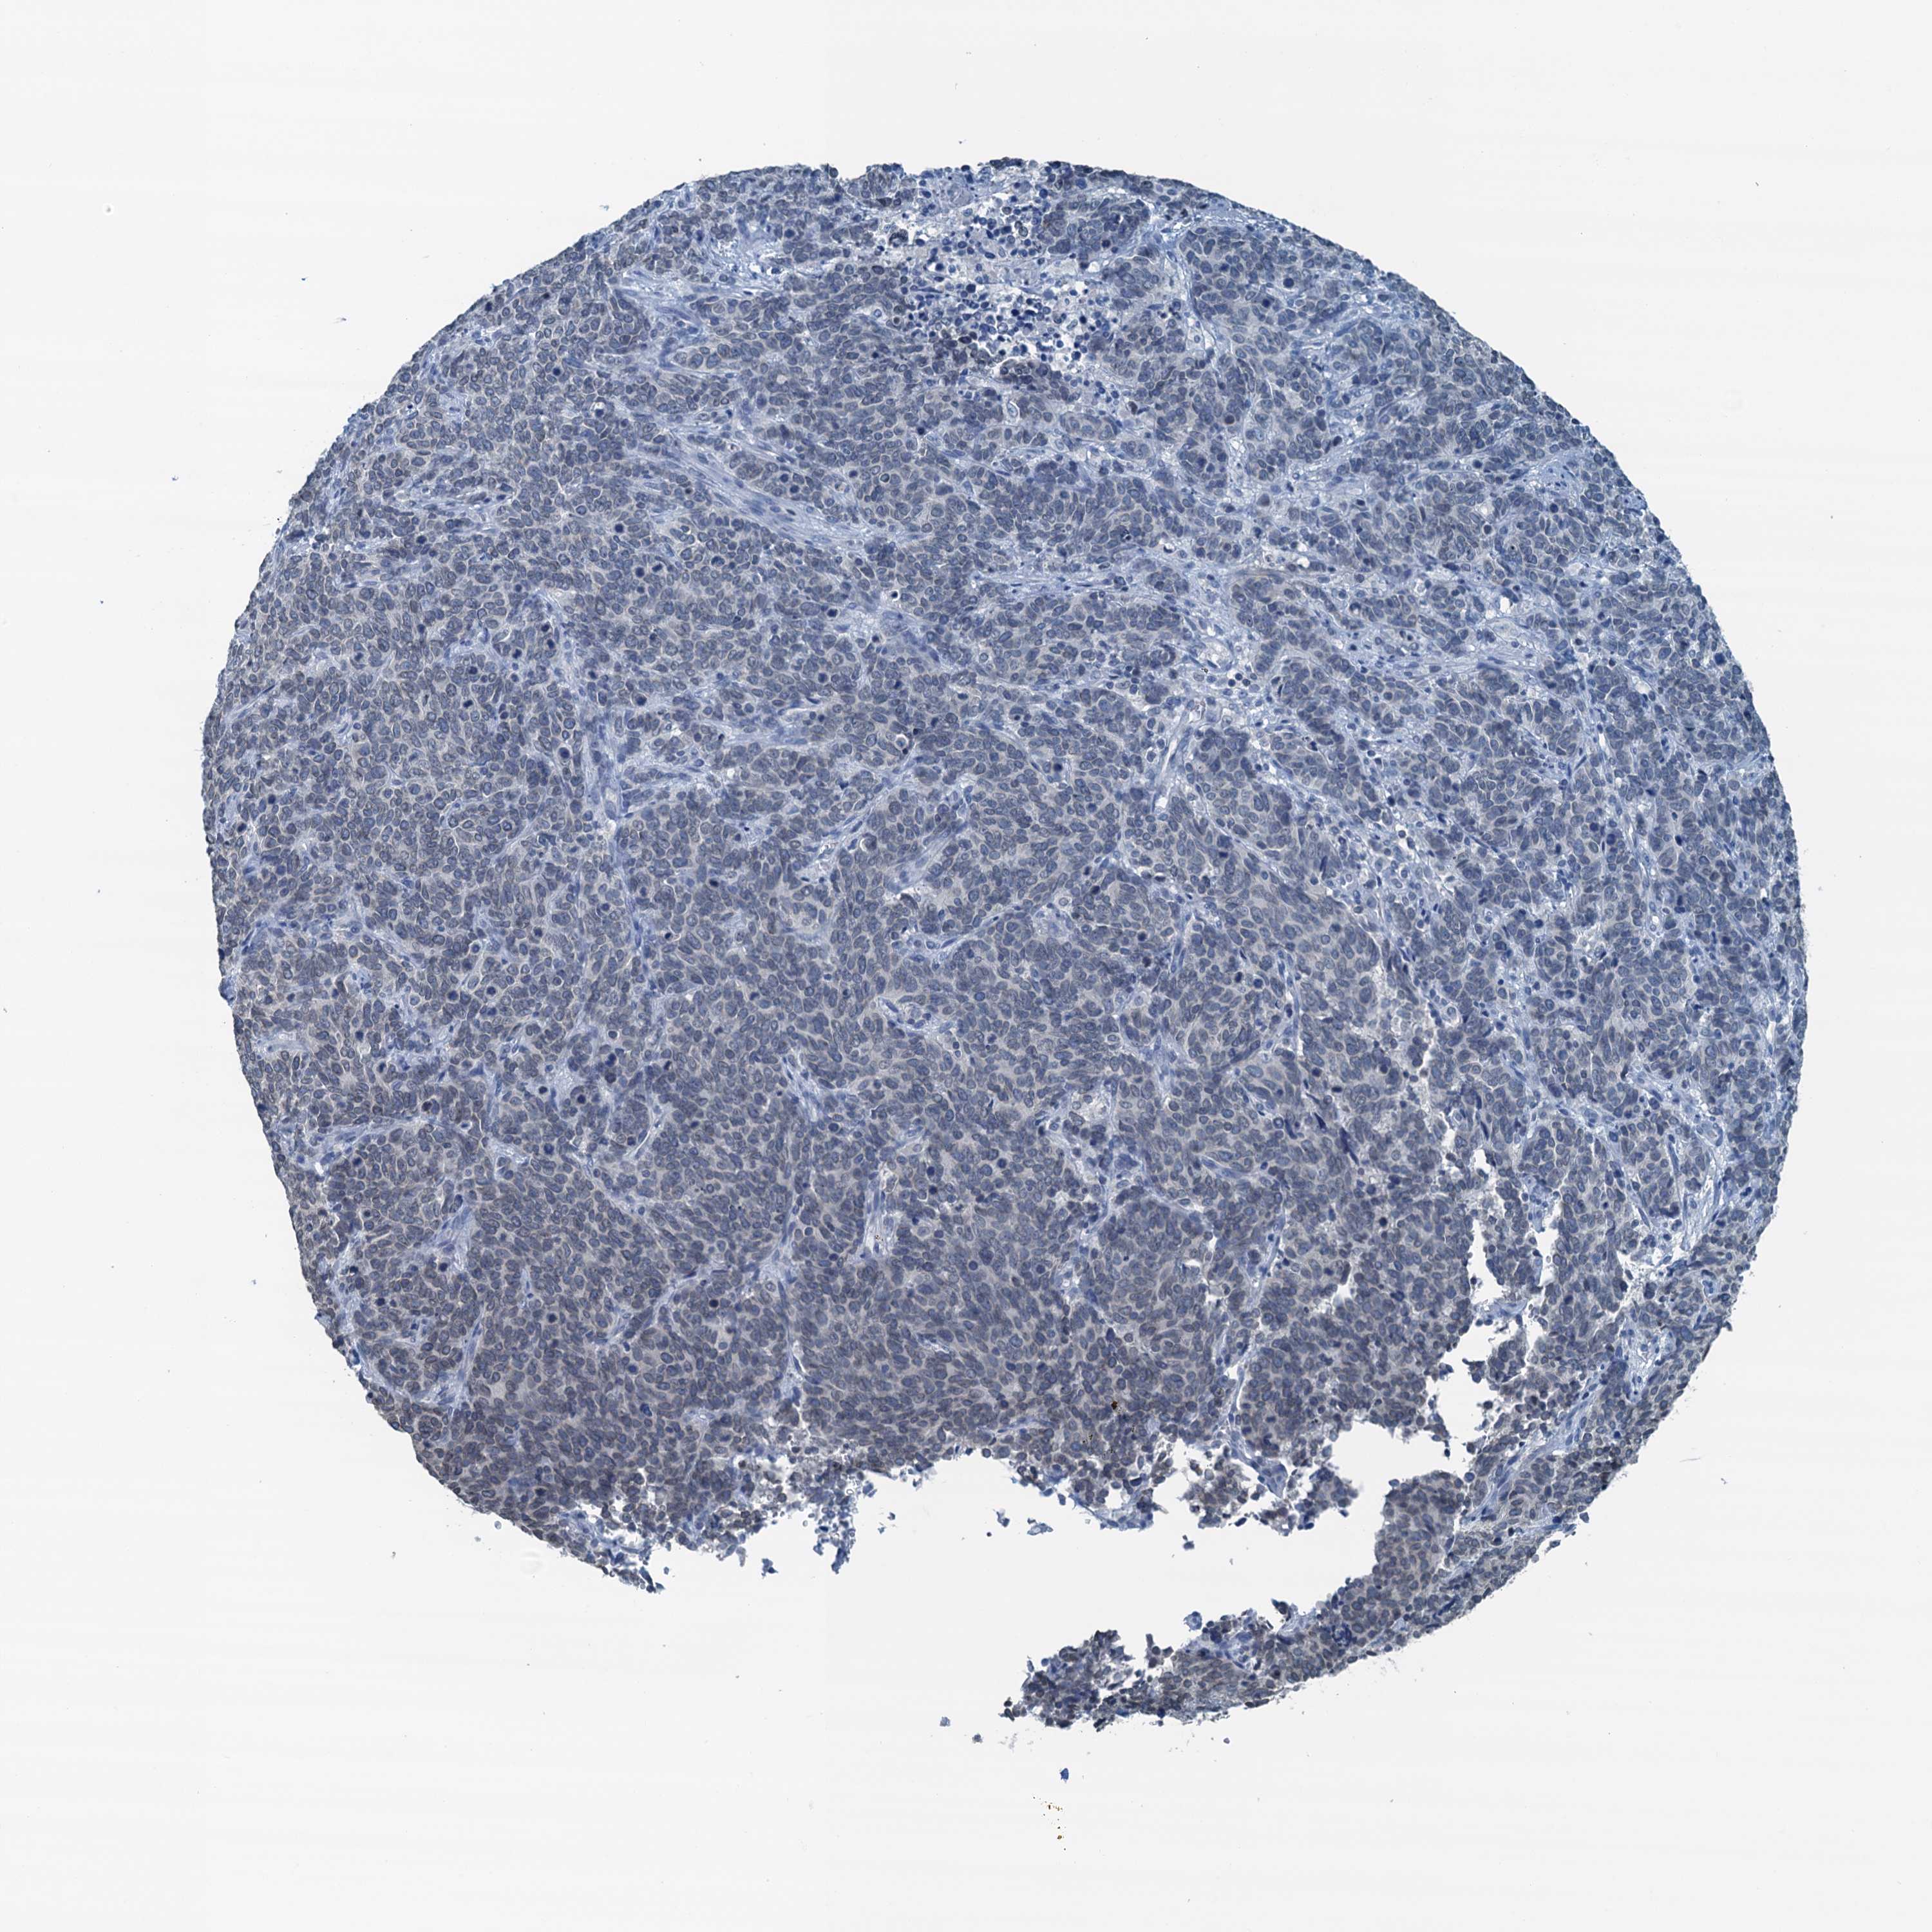

CERVICAL CANCER - Protein expressioni

A mouse-over function shows sample information and annotation data. Click on an image to view it in a full screen mode. Samples can be filtered based on level of antibody staining by selecting one or several of the following categories: high, medium, low and not detected. The assay and annotation is described here.

Note that samples used for immunohistochemistry by the Human Protein Atlas do not correspond to samples in the TCGA dataset.

Antibody stainingi

Antibody staining in the annotated cell types in the current human tissue is reported as not detected, low, medium, or high, based on conventional immunohistochemistry profiling in selected tissues. This score is based on the combination of the staining intensity and fraction of stained cells.

Each image is clickable and will lead to virtual microscopy that enables deeper exploration of all samples and also displays staining intensity scores, fraction scores and subcellular localization as well as patient and tissue information for each sample.

Antibody HPA040511

Staining

High

Medium

Low

Not detected

Intensity

Strong

Moderate

Weak

Negative

Quantity

>75%

75%-25%

<25%

None

Location

Nuclear

Cytoplasmic/membranous

Cytoplasmic/membranous,nuclear

Squamous cell carcinoma, NOS

Adenocarcinoma, NOS